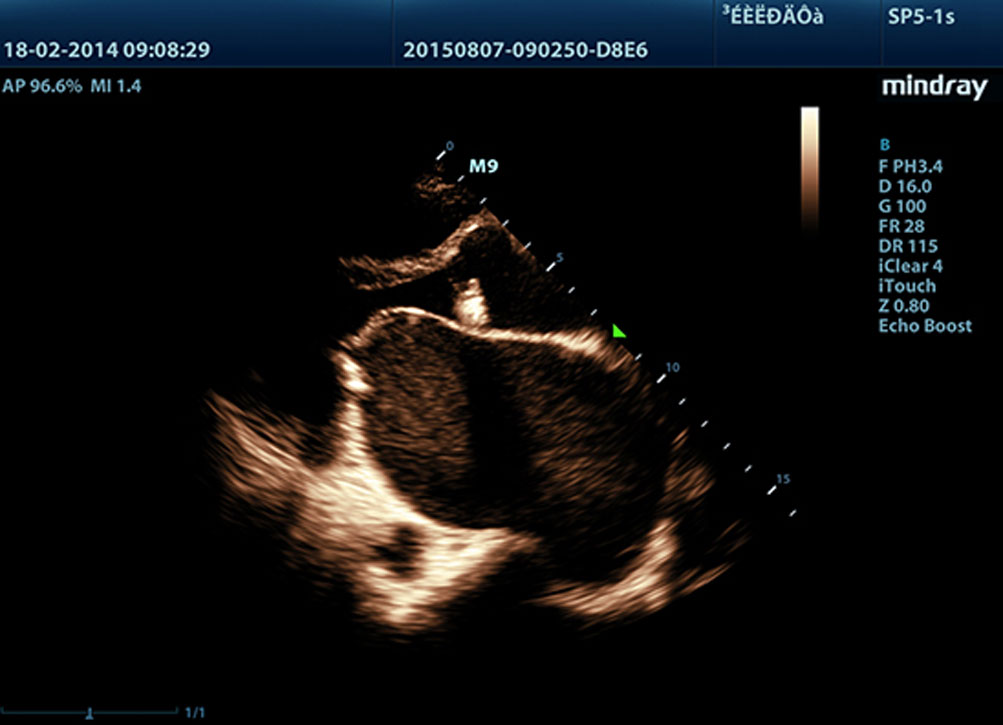

Echo Boost?

Mindrays einzigartige adaptive Signalverarbeitung mit intelligenter Echoerkennung, die zwecks Nutzung der nat├╝rlichen Signal-zu-Rauschen-Information zur Verst?rkung der schwachen Echosignale bei gleichzeitiger Unterdr├╝ckung der diversen Umgebungsger?usche entwickelt wurde, liefert eine ausgeglichenere Brillanz der Bilder und eine verbesserte Visualisierung der Gewebsschichten des Myokards.